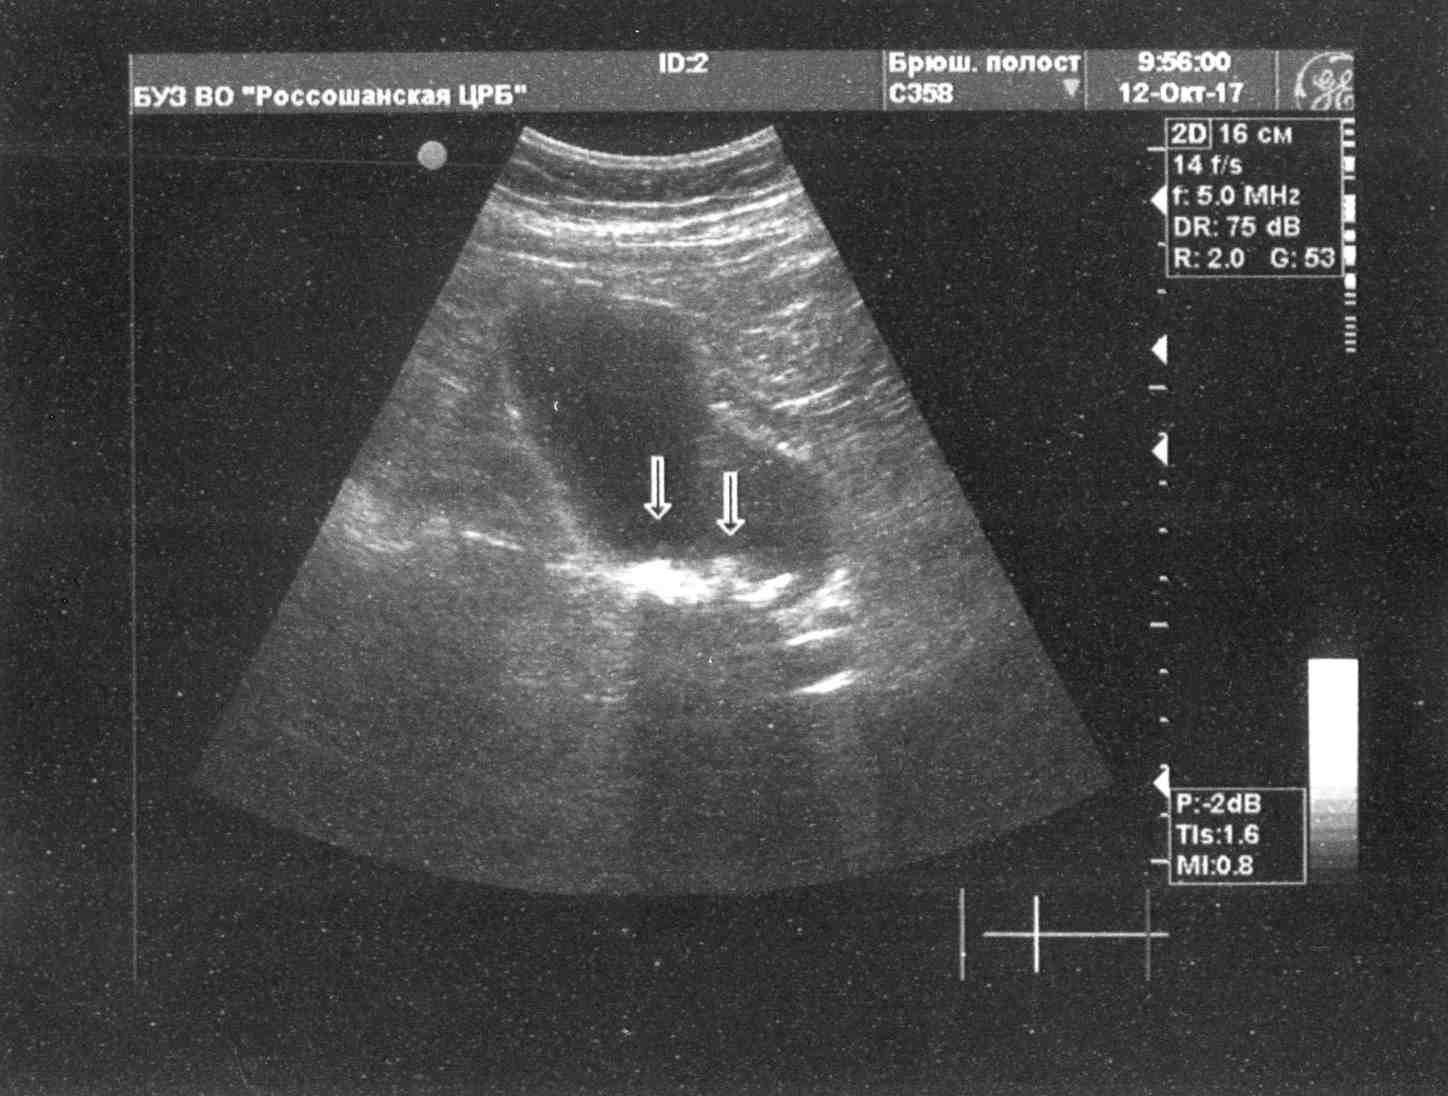

Вот только получилось взять УЗИ у отца.

Посмотрите, пожалуйста.

Есть плюсы и минусы по УЗИ (в сравнении со старым).

Печень стала больше, портальная вена - тоже. Селезенка увеличена, что часто бывает при высоком фиброзе.

Описание УЗИ желает быть лучшим... Очень неполное.

В желчном включения стали меньше по размерам - это хорошо!

В левой доле печени округлое эхо-включение (гемангиома, вроде), что раньше не было.

Нужна консультация гастроэнтеролога.

Раз в полгода нужно повторять УЗИ - отслеживать эти включения (и в желчном, и в печени).

Для верификации образований в печени я бы провел КТ желательно с в/в рентгеноконтратом если позволяют почки.

Креатинин крови в норме? При повышенном рентгеноконтраст может быть опасен.

УЗИ для верификации недостаточно.

Можно расценивать её размер, как предельный вариант нормы.

Более детальную картину должна дать КТ.